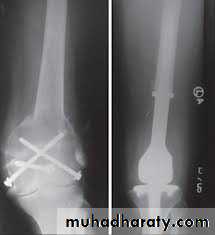

More aggressive tumours, and recurrent lesions, should be treated by excision followed,

if necessary, by bone grafting or

prosthetic replacement.